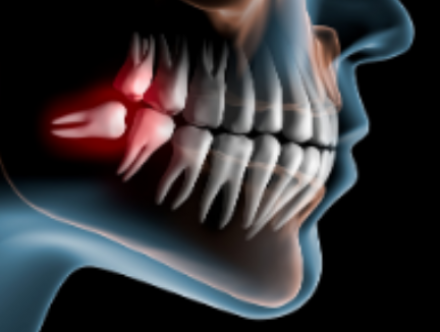

親知らずについて

親知らずの知識

親知らずは全て抜いたほうが良いのか?